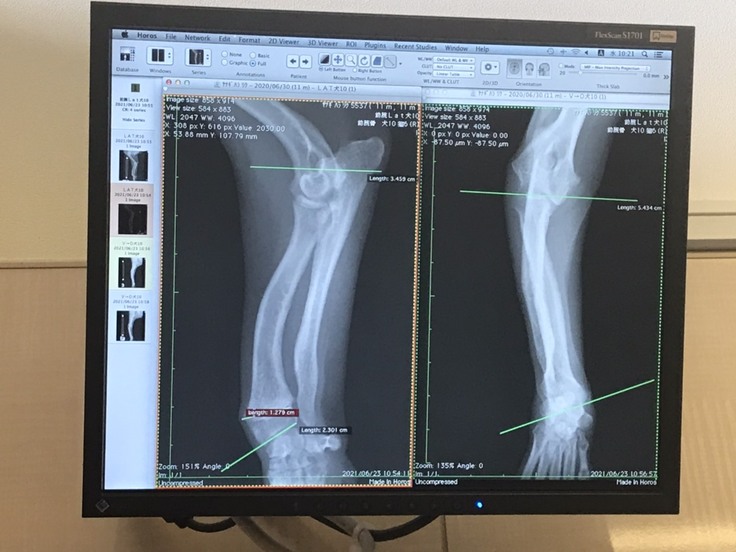

まず、レントゲン所見ではやはり手術適応に入るとのことです。ですがりくの場合は複雑に変形してしまっていて(これもミックス犬のせいだと思われます)、リスクも高い手術で整形専門の病院でやらなければならないことは勿論、やったとしても完全完治にはならないと。

(本来平行にならなければいけない関節が、緑線で曲がっていることが分かります)